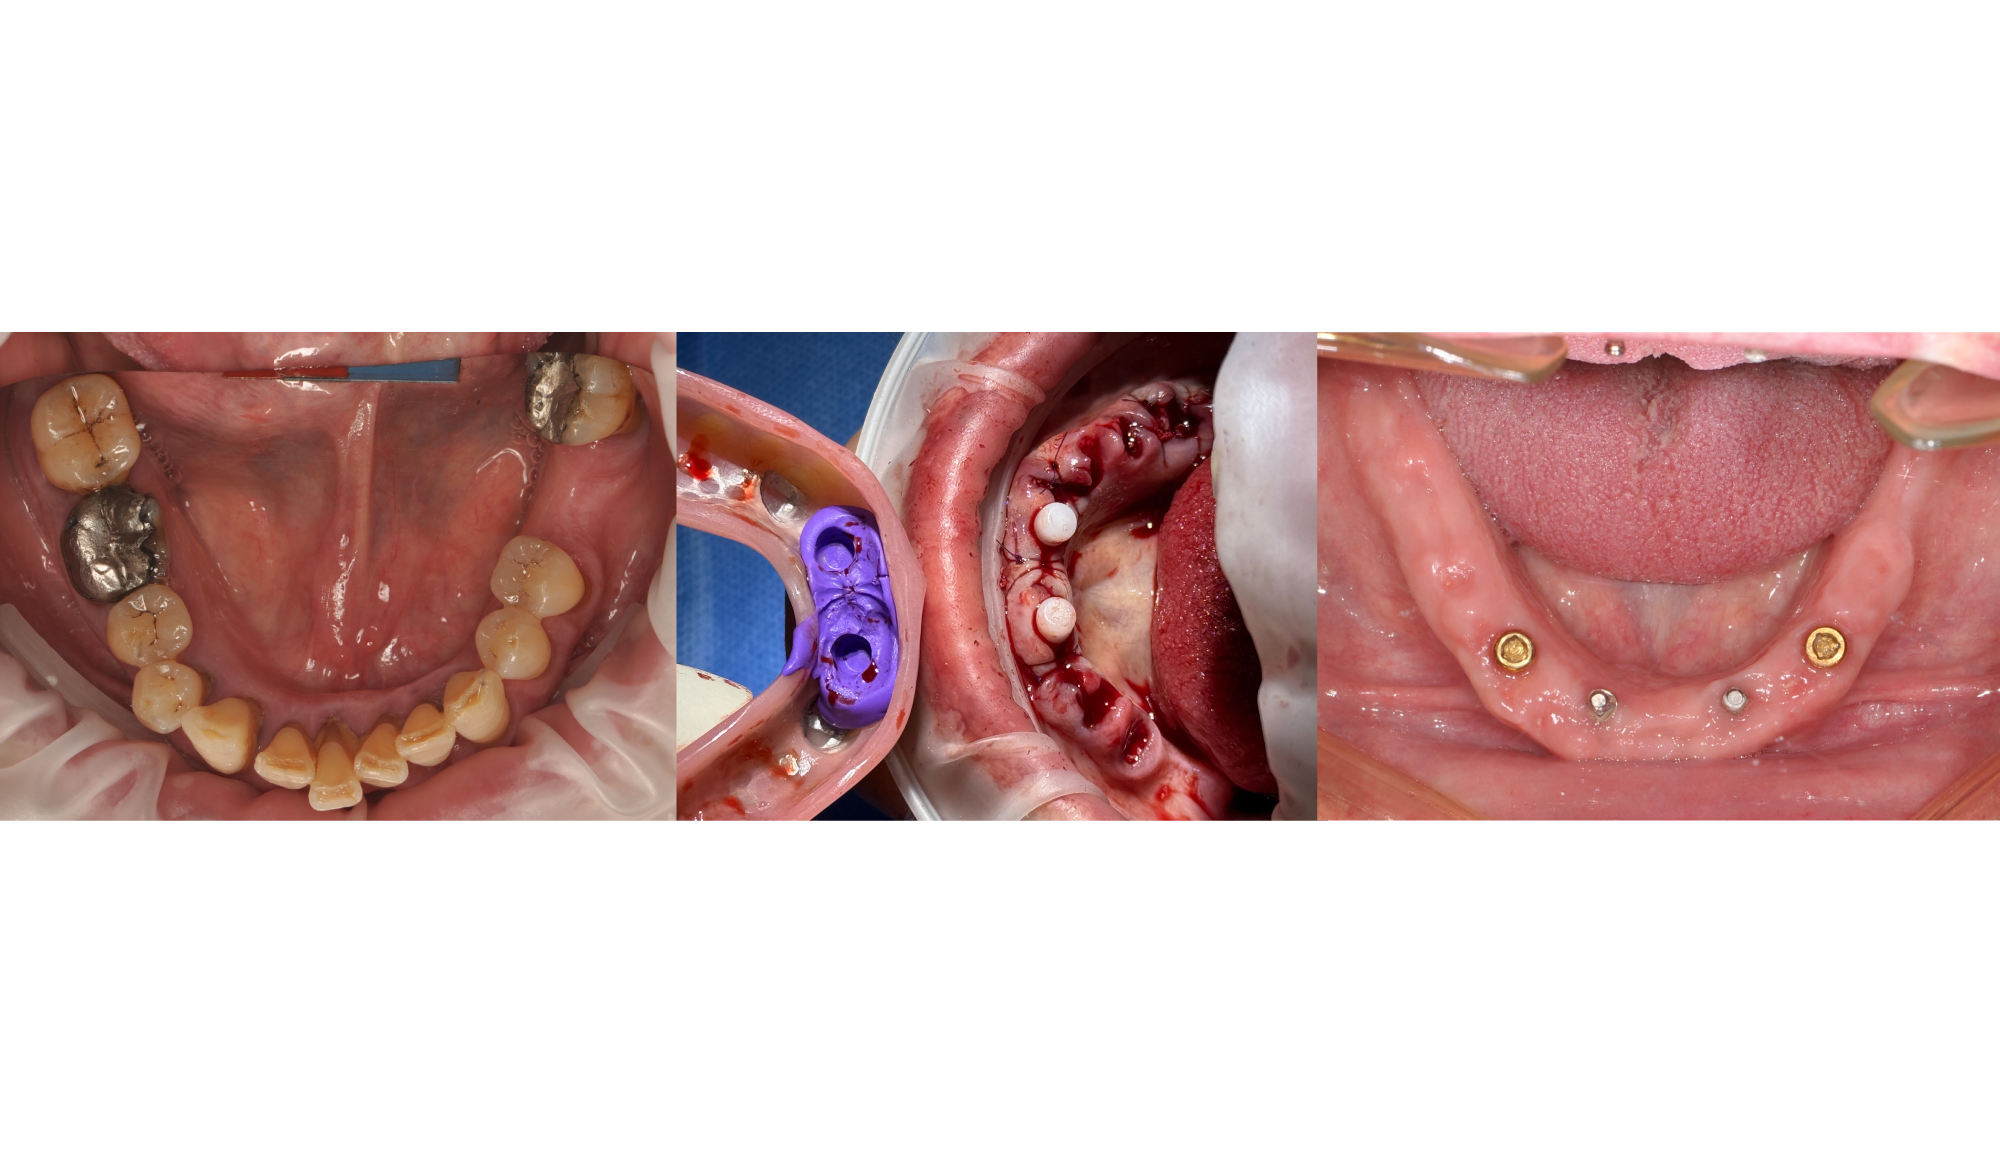

Director’s Clinical Cases

Director’s Clinical Cases